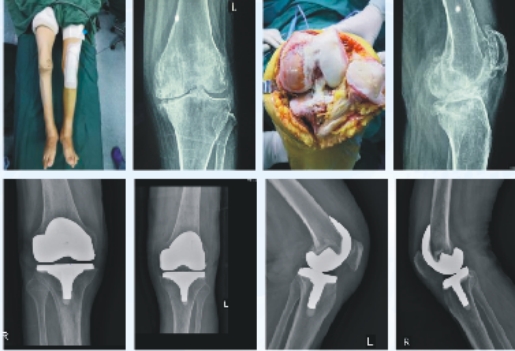

人工膝关节置换术

适用:膝关节骨关节炎、类风湿性关节炎和强直性脊柱炎的膝关节晚期改变、创伤性骨性关节炎、其他非感染性关节炎、大骨节病、血友病性关节炎等、感染性关节炎已治愈或静息、膝关节关节面的肿瘤切除后。

优势:术后恢复快、关节功能贴合生理状态

晚期治疗:以关节置换术为主,包括单髁置换、全膝置换术。